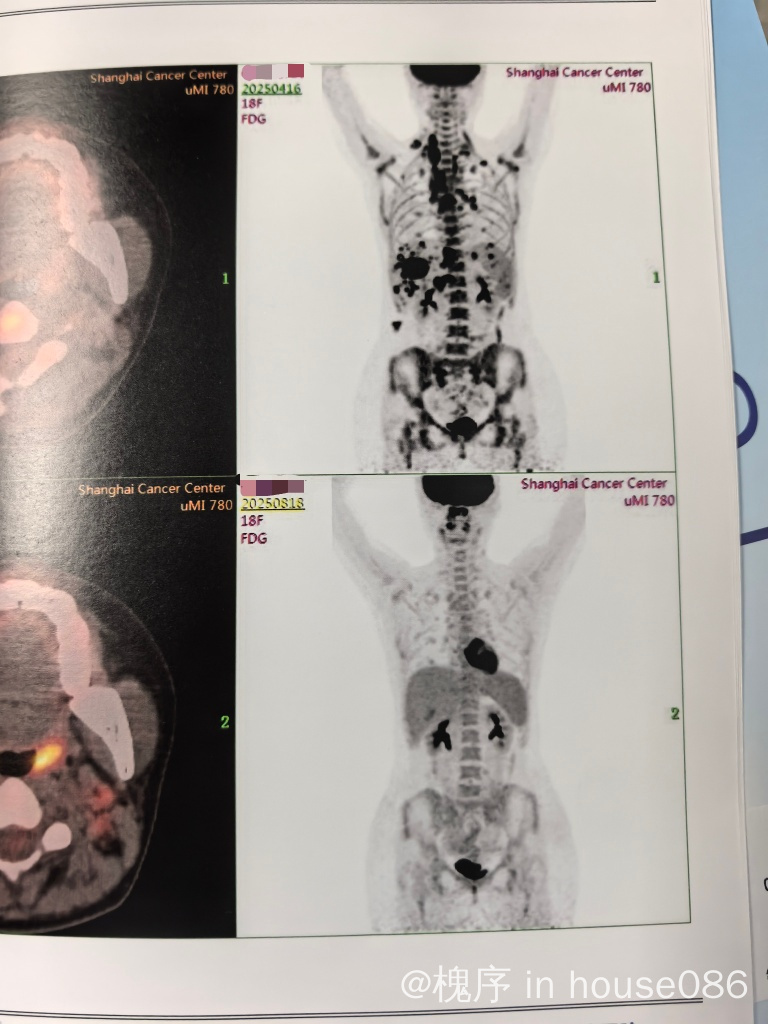

接着去上海大型专科医院进行病理会诊与PETCT检查,确定为四期(其实分期也就是确定一下疗程多少,不要太害怕)当时情况紧急没进行生育力保护,借用主治的话“先保命要紧”(药物损伤不是完全没有,生理期已经出走将近一年)

治疗中途评估是二疗后十四天进行胸腹部增强CT判断肿大淋巴结大幅度减小,以及四疗后二十一天进行的PETCT确定活性降低到肝脏代谢持平(勉强3分cr)六疗后一个月进行PETCT确定原发病灶无明显异常摄取(大概是1分)